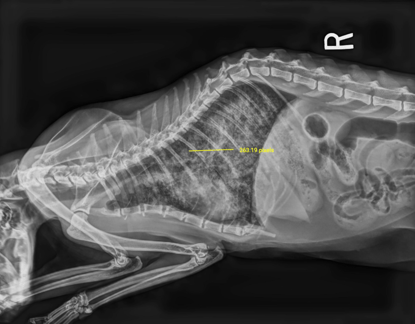

The same image in JPEG format might only show “263.19 pixels” which is a meaningless value for medical purposes.

In contrast, JPEGs strip out this data, leaving only the image itself. Measurements like “263.19 pixels” become medically meaningless because we can’t convert them into millimeters or centimeters without knowing the original scale (example below)